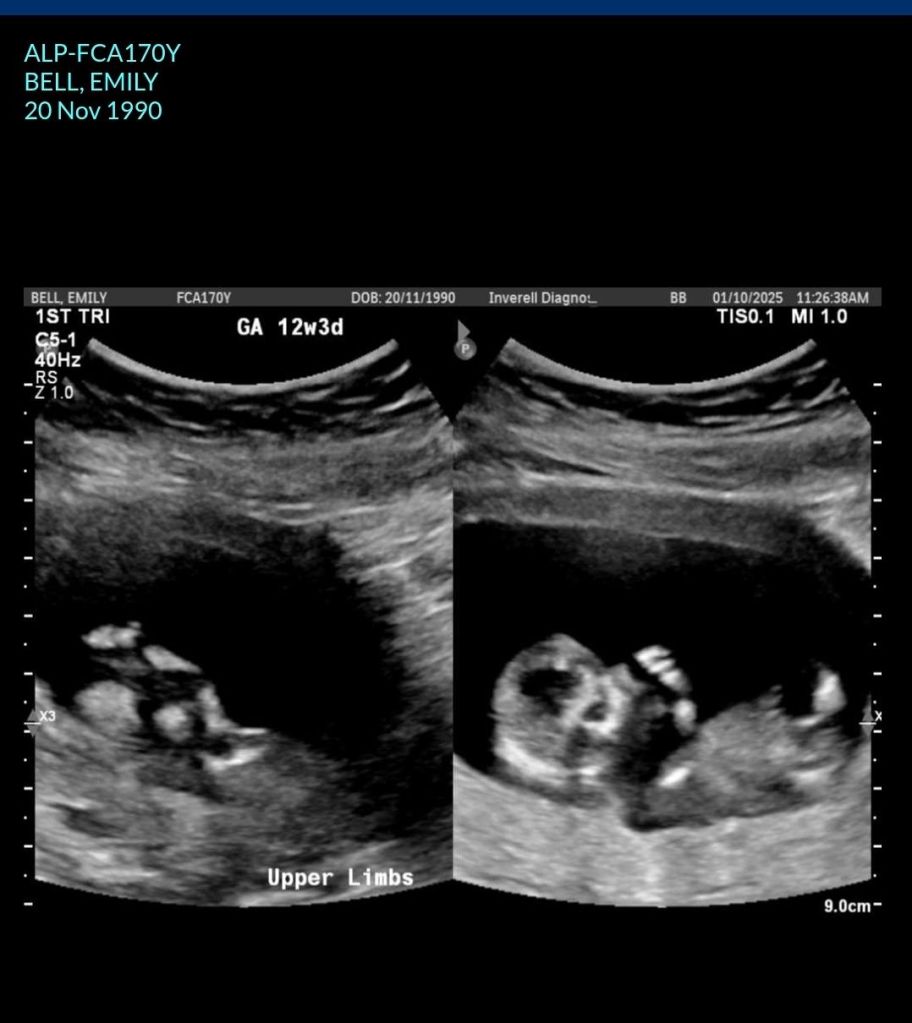

I couldn’t believe it. So I rang doctors the Friday and got into see him straight away. And I walked in and had the test in my wallet. He said how can I help you today Emily. I said I think I know why I have been so sick. He said oh yes whys that. So I pulled the test out and gave it to him. He got me to do bloods to confirm. All came back on Monday and yes I was. So we booked an ultrasound and that Friday I got in. And we saw you for the first time. 8.5 weeks old. We your parents were so surprised, happy, overwhelmed, and just amazed.

Every blood test and ultrasound I have had, you my son have been perfectly healthy. Couldn’t ask for better. You are growing well. You are healthy. You are a miracle and such a blessing. After everything I have been through for the last 12 years. I am so surprised everything is perfect. Its so Surreal. And everyone keeps saying how good I look. Glowing. Pregnancy suits you. Even along our journey I am still in awe. Still cant believe you are there. That you exist in me.